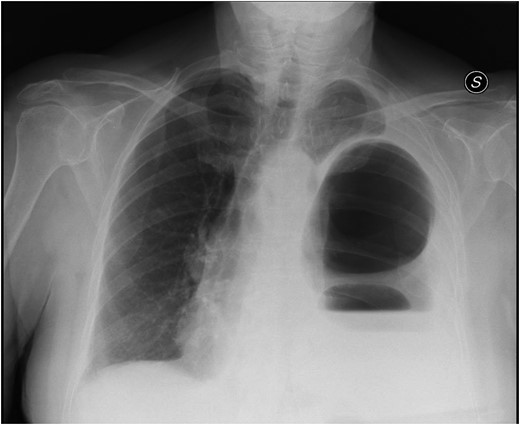

Thoraco-abdominal computed tomography (CT) showed the herniated bowel (transverse colon), translocated through a defect of about 7 cm in the left hemidiaphragm (Figs 2–4), a rightward deviation of the mediastinal structures and an atelectasis of the left lung (Fig. 5). The left colon had the appearance of a volvulus.

CT of chest showing defect on left side of the diaphragm and colon herniation in the thoracic cavity.